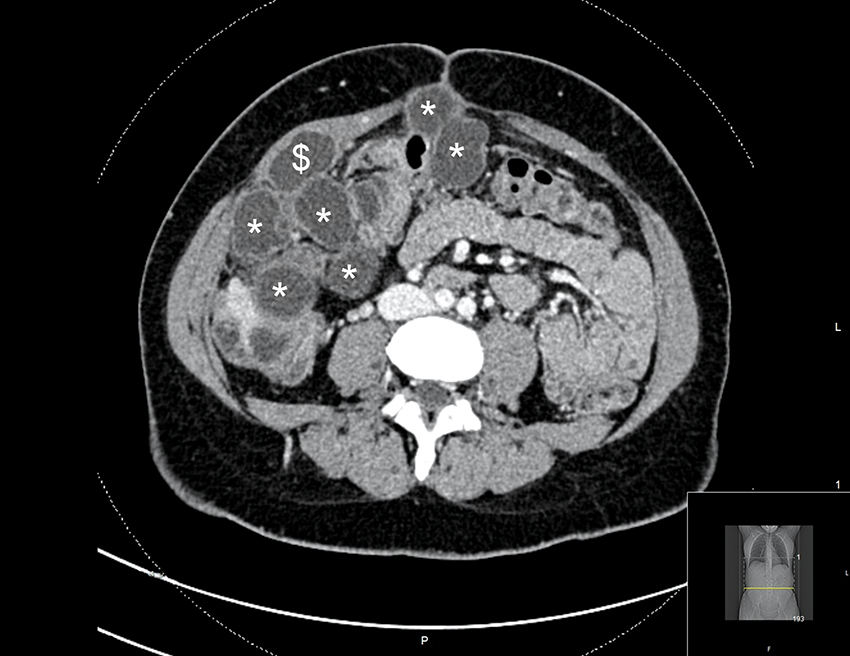

En kvinne i 30-årene hadde noen år tidligere fått påvist en solitær levercyste i forbindelse med utredning for magesmerter. Cysten ble behandlet med perkutan drenasje og sklerosering. Grunnet raskt residiv ble det utført kikkhullskirurgi med delvis fjerning av cysteveggen (laparoskopisk fenestrering) tre måneder senere. Cysteveggen ble sendt til histopatologisk undersøkelse, som ikke viste patologi i veggen eller parasittsykdom. Fra tidligere hadde pasienten diabetes mellitus type 1 og ulcerøs kolitt. Blodsukkeret var velregulert med insulinpumpe. To år etter fjerning av cysteveggen var hun fortsatt plaget med magesmerter. CT viste tallrike cyster i leveren og bukhulen fra diafragma til bekkenbunn (figur 1). Mistanken om parasittinfeksjon ble reist på nytt, og regranskning av cysteveggen fra operasjon to år tidligere var forenlig med dette. Serologisk prøve bekreftet infeksjon med parasitten Echinococcus granulosus.

To cyster var utilgjengelige for reseksjon uten omfattende organreseksjon. Disse ble først aspirert, deretter ble hypertont saltvann instillert før fenestrering og uthenting av dattercyster (figur 2). Under operasjonen rumperte to cyster spontant. Grunnet cysteruptur ble bukhulen avslutningsvis skylt med 2 liter hypertont saltvann i ti minutter. Saltvannet ble sugd ut, og bukhulen ble skylt i to runder med fysiologisk (0,9 %) saltvann. Pasienten var stabil under inngrepet, men var pressorkrevende. Operasjonen varte i totalt 12 timer.